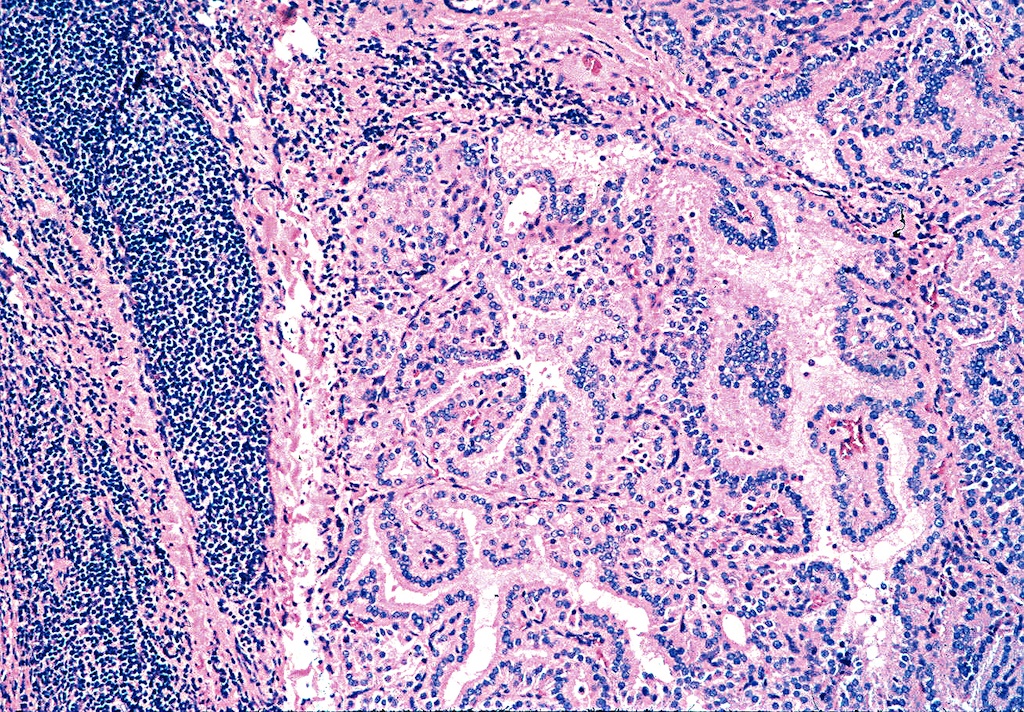

Graves Disease Histology Hashimoto Thyroiditis Pathology Student Thyroid Antibodies In Graves Disease The two types of antibodies linked with graves’ disease. It is caused by an antibody. Diagnostic tests are suppressed serum tsh, elevated levels of circulating thyroid hormones, detectable tsh receptor antibodies,. The antibodies in graves’ disease bind to receptors on the surface of thyroid cells and stimulate those cells to overproduce and. Graves disease is the most common cause of. Thyroid Antibodies In Graves Disease.